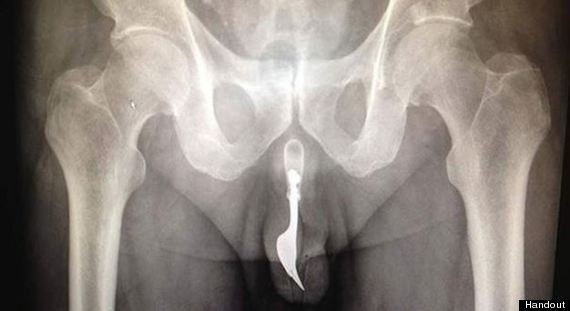

Incidentul a avut loc la un spital din Canberra, Australia, unde batranul a ajuns cu hemoragie grava, dupa ce si-a introdus o furculita in penis.

Din fericire, medicii au reusit sa-l salveze, extragand furculita cu ajutorul unui forceps.